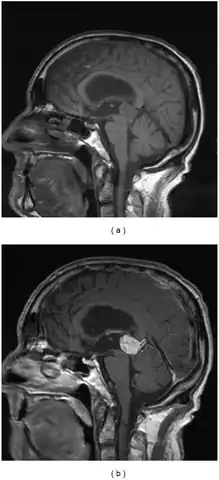

Diagnosis can be made via combination of physical exam, particularly deficits of the relevant cranial nerves. Confirmation can be made via imaging, such as CT scan or MRI.